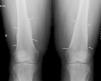

Hombre de 45 años, que es remitido a la consulta de Reumatología por dolores articulares difusos en muñecas y rodillas. El paciente está diagnosticado de cirrosis hepática con hepatocarcinoma y síndrome hepatopulmonar grave. En la exploración física presenta tumefacción de rodillas y muñecas (artritis) y acropaquias. En el estudio radiológico convencional solicitado se observa un engrosamiento perióstico continuo, grosero y ondulante, en localización diafisometafisaria de cúbito y radio en ambos antebrazos y de predominio en fémures distales en ambas rodillas, compatible con reacción perióstica no agresiva. En la figura 1 se observa el engrosamiento perióstico en ambos fémures afectando el borde cóncavo del hueso y respetando las epífisis, e igual afectación de cúbito y radio en la muñeca derecha, en la figura 2.

Los hallazgos a la exploración física de acropaquias –dedos en palillo de tambor– y artritis con tumefacción en manos y rodillas, así como la presencia en la radiografía de una periostitis continua de apariencia no agresiva afectando al borde cóncavo de los huesos largos tanto de las extremidades superiores como de las inferiores permitió establecer el diagnóstico de osteoartropatía hipertrófica. Esta entidad clínica se asocia fundamentalmente a procesos intratorácicos (sobre todo neoplásicos, especialmente el carcinoma broncogénico y tumores pleurales), aunque también a otras patologías entre las cuales se incluye la enfermedad hepática (hepatocarcinoma, hepatitis alcohólicas y la cirrosis hepática, tanto biliar como portal)1–3.